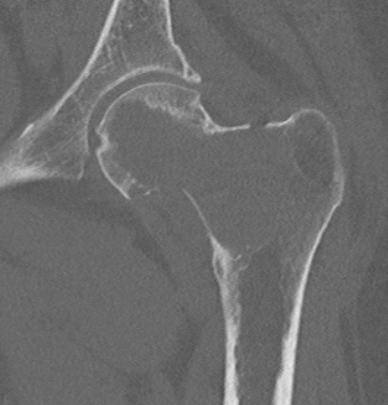

CT

MRI

Low signal intensity T1 / high signal intensity T2

Areas of ABC seen in 10 - 14%

Look for signs of grade III: soft tissue extension

Imaging

Grade III with cortical destruction and soft tissue extension